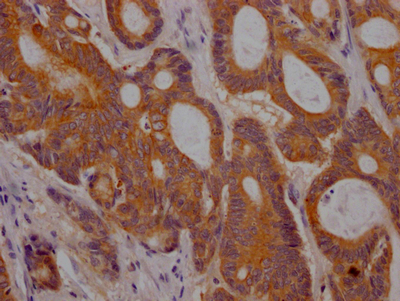

CSB-RA280380A0HU

IHC image of CSB-RA280380A0HU diluted at 1:100 and staining in paraffin-embedded human colon cancer performed on a Leica BondTM system. After dewaxing and hydration, antigen retrieval was mediated by high pressure in a citrate buffer (pH 6.0). Section was blocked with 10% normal goat serum 30min at RT. Then primary antibody (1% BSA) was incubated at 4℃ overnight. The primary is detected by a Goat anti-rabbit IgG polymer labeled by HRP and visualized using 0.05% DAB.